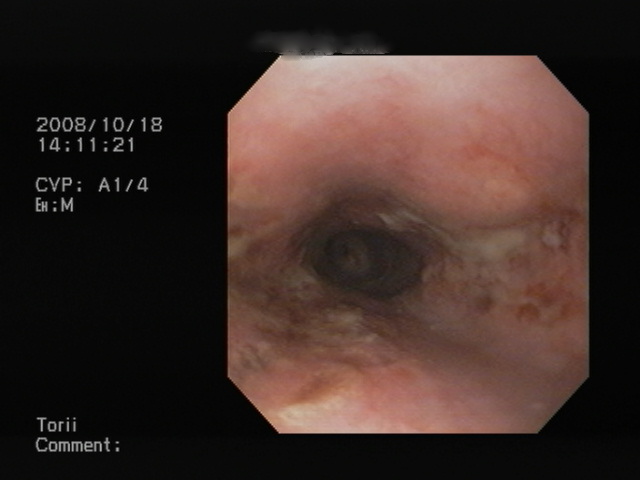

胃の中の写真です。

バラバラになった、食べ物が認められます。

これで、ワンちゃんも(夢叶い)おやつを無事食すことができました。(笑)

実は胃の中から再度摘出を検討したのですが、やはりバラバラになった食べ物を取り出すことができず断念です。もともとおやつでしたので、これで一件落着と・・・